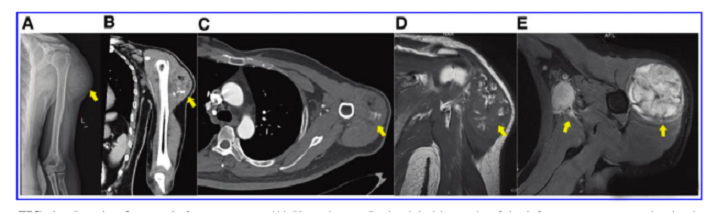

接受iPS細(xì)胞治療患者的畸胎瘤。(A) 在左上臂的三角肌中,觀察到一個(gè)圓形的混合密度腫塊,邊界不清,為9.6±5.2cm。(B) CT冠狀掃描顯示三角肌內(nèi)有一圓形混合密度腫塊,邊界不清。(C)增強(qiáng)CT軸向掃描顯示不均勻和中度強(qiáng)化。(D)MRI T1W以等信號(hào)為主,有不規(guī)則的高低信號(hào)區(qū)。(E) T2W也顯示高信號(hào)和斑片狀低信號(hào)區(qū),左腋窩有多個(gè)淋巴結(jié)腫大。

文中展示了該未成熟畸胎瘤的臨床,放射學(xué)和病理學(xué)特征,作者認(rèn)為這種腫瘤不同于典型的未成熟畸胎瘤,特點(diǎn)是快速增長(zhǎng)和局部淋巴結(jié)轉(zhuǎn)移,該新生腫瘤對(duì)典型化療方案沒有反應(yīng),磁共振成像顯示腫瘤的不均勻強(qiáng)化和豐富的血供。